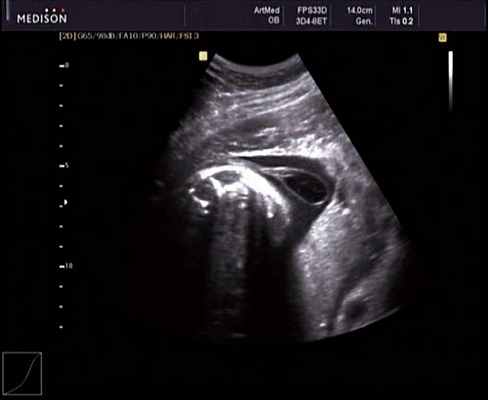

Клиническое наблюдение 2

Беременная М., 21 года. Впервые обратилась в клинику в срок 20 нед беременности. Исследование проводилось на аппарате SonoAce-R7 (Samsung Medison) с использованием режима поверхностной объемной реконструкции 3D/4D. При изучении позвоночника плода в трех плоскостях костных деформаций не выявлено. В грудном отделе позвоночника обнаружено тонкостенное кистозное образование с анэхогенным содержимым, стебельчатой формы (рис. 10-12). Степень "прозрачности" содержимого была выше околоплодных вод, что позволяло идентифицировать его как ликвор. В проекции грыжевого выпячивания располагалась петля пуповины, дифференциальную диагностику которой без труда удалось провести с помощью ЦДК (рис. 13).

Рис. 10. Беременность 20 нед. Менингоцеле: типичное кистозное образование стебельчатой формы.

Рис. 11. Беременность 20 нед. Менингоцеле.

Рис. 12. Менингоцеле. В сагиттальном срезе видна неровность кожи в проекции расщелины.

Рис. 13. Петля пуповины в режиме ЦДК.

У плода наблюдалась выраженная гидроцефалия, обусловленная синдромом Аронольда - Киари II (рис. 14, 15).